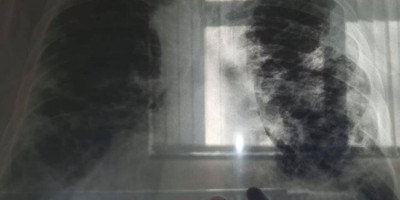

Posle dve decenije neprekidnog pada, u Evropi se povećao broj umrlih od tuberkuloze, upozorila je u petak Svetska zdravstvena organizacija (SZO), dodajući da je u dve zemlje taj porast očigledan!

U 2021. godini ova plućna bolest je ubila 27.300 Evropljana, u poređenju sa 27.000 prethodne godine, prema poslednjim dostupnim podacima.

Sa 4.900 i 3.600 procenjenih smrtnih slučajeva, Rusija i Ukrajina su najviše pogođene zemlje. Prema SZO, ovo povećanje je uzrokovano relaksacijom dijagnostičkih procedura tokom karantina povezanih sa pandemijom kovida-19 i širenjem soja tuberkuloze koji je otporan na antibiotik propisan za ovu bolest.

To je prvi put u 20 godina da je trend obrnut, navela je SZO. U 53 zemlje oko 230.000 ljudi je obolelo od tuberkuloze, bolesti izazvane bakterijom koja uglavnom napada pluća – ovaj ukupan broj je, međutim, i dalje manji nego prethodnih godina.

"Povećanje broja smrtnih slučajeva uzrokovanih tuberkulozom u 2021. je vrlo verovatno posledica kašnjenja ili odsustva dijagnoze tuberkuloze zbog poremećaja medicinskih usluga tokom pandemije kovida-19", saopštila je SZO Evropa.

Pored toga, prevalencija tuberkuloze rezistentne na lekove takođe se značajno povećala, pošto su jedna trećina dijagnostikovanih slučajeva bili slučajevi tuberkuloze rezistentne na rifampicin 2021. godine. Na globalnom nivou, SZO je već u oktobru 2022. izrazila zabrinutost zbog sličnog porasta, takođe prvi put zabeleženog u poslednjih 20 godina, novih slučajeva tuberkuloze otkrivenih 2021. godine.